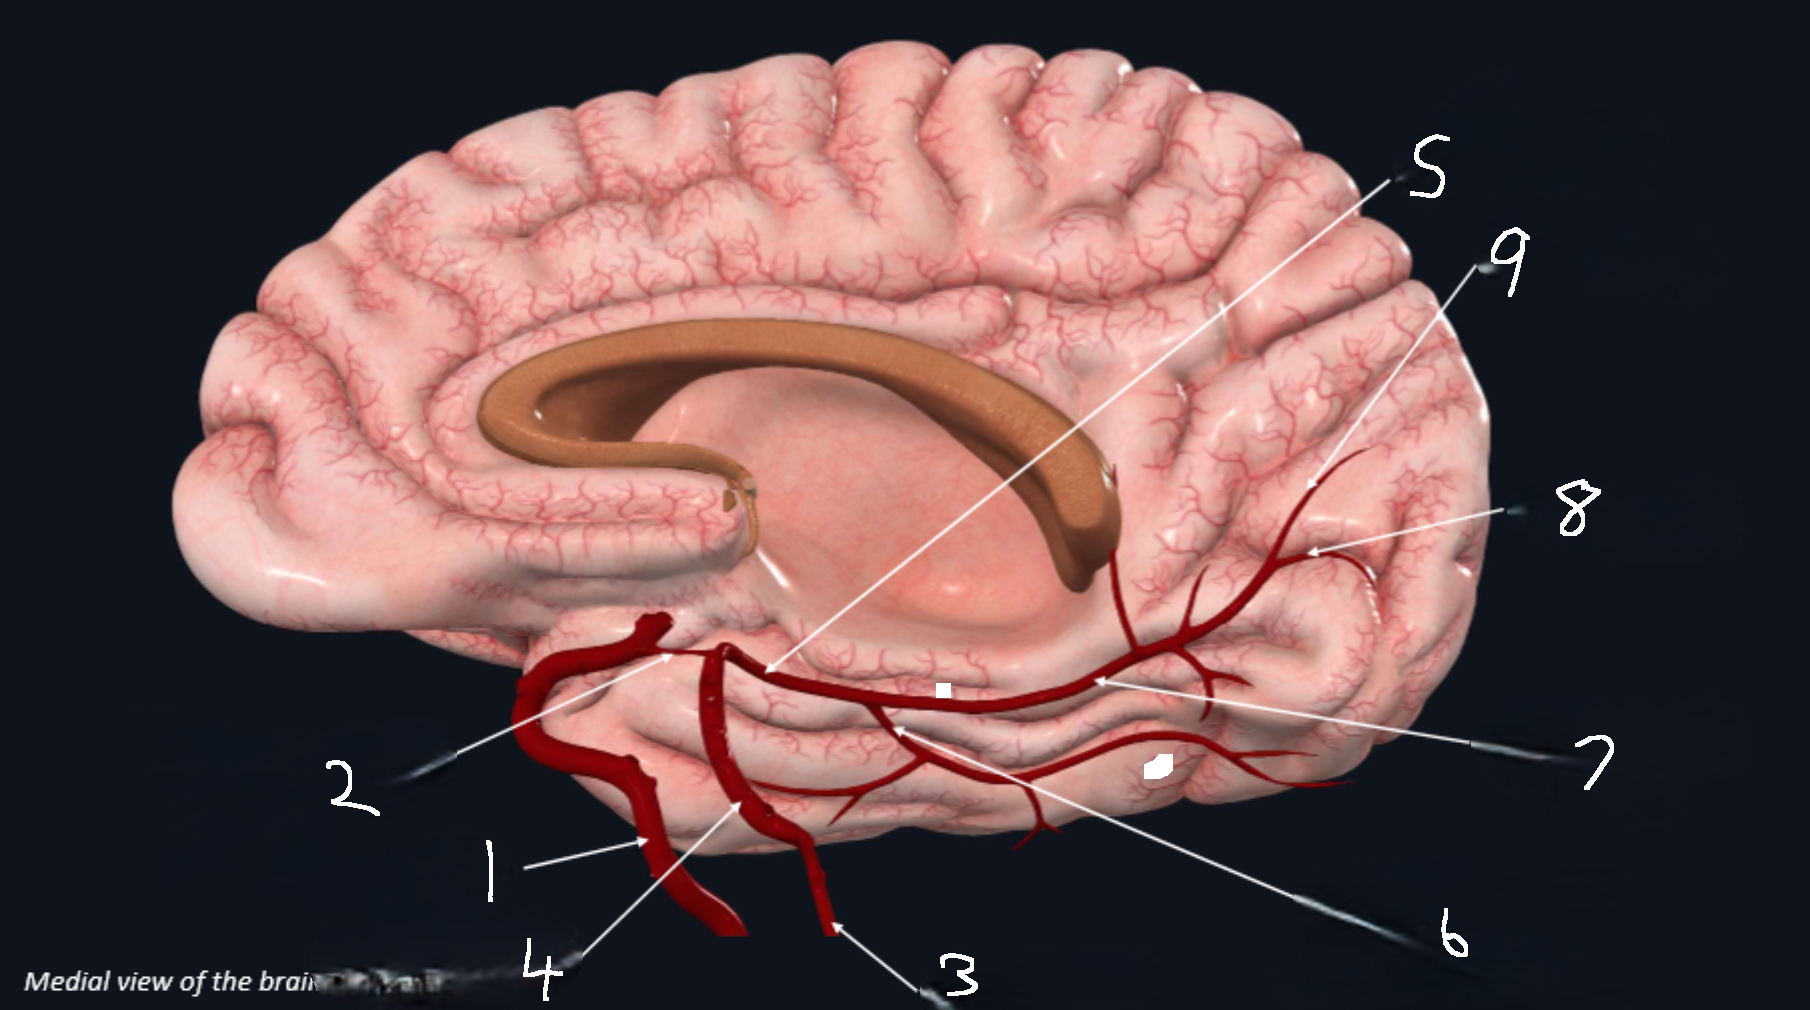

What is 1?

internal carotid artery

What is 2?

anterior cerebral artery

What is 3?

frontopolar artery

What is 4?

pericallosal artery

What is 5?

callosomarginal artery

What is 6?

corpus callosum